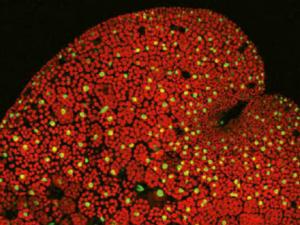

Desvelan cómo estalla la resistencia a antibióticos en una bacteria agresiva

Un equipo internacional de científicos, liderado por españoles, ha logrado desvelar cómo se dispara el mecanismo de resistencia a los antibióticos en 'Pseudomonas', una bacteria multiresistente con gran incidencia en los hospitales y responsable, entre otras, de infecciones pulmonares y respiratorias.&#13;